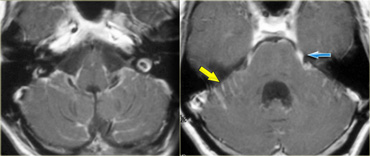

Schwannoma in CPA-region with typical features of an extraaxial tumor (T2WI) Schwannoma in CPA-region with typical features of an extraaxial tumor (T2WI)

The T2W-images show a schwannoma located in the cerebellopontine angle (CPA).

This case nicely demonstrates the typical signs of an extra-axial tumor.

There is a CSF cleft (yellow arrow).

The subarachnoid vessels that run on the surface of the brain are displaced by the lesion (blue arrow).

There is gray matter between the lesion and the white matter (curved red arrow).

The subarachnoid space is widened because growth of an extra-axial lesion tends to push away the brain.

All these signs indicate that this is a typical extra-axial tumor.

In the region of the CPA 90% of the extra-axial tumors are schwannomas.